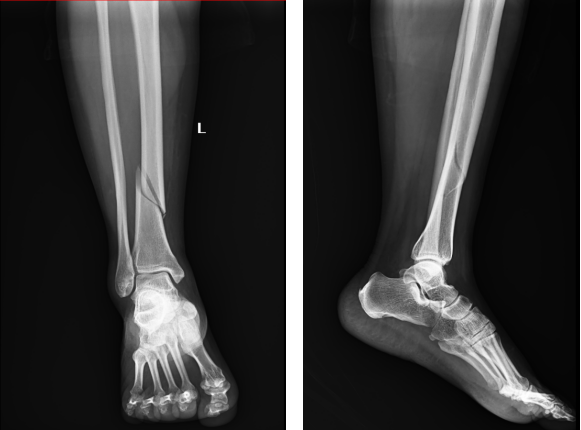

患者陈女士因意外跌伤,导致左小腿肿痛并伴有功能障碍,随即紧急前往我院外科就诊。入院后,外科医师团队迅速对陈女士进行了全面的身体检查,并结合其病史、体征及清晰的影像学检查,明确诊断为左侧胫骨下段骨折。

手术过程顺利,术后的影像学检查显示,骨折部位得到了精准复位和固定。与传统的骨折切开复位钢板内固定手术相比,此次采用的髓内钉内固定术具有切口小、创伤少、固定效果好等显著优势,极大地缩短了骨折愈合时间和患者行动能力的恢复周期,有效减轻了患者的痛苦。